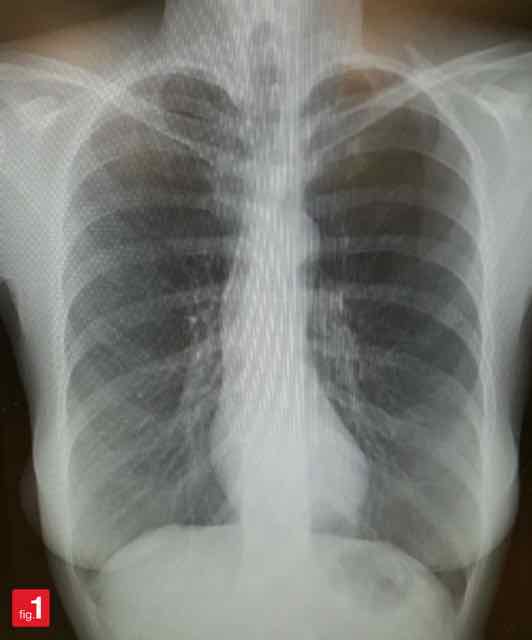

Raio X Como Fazer Uma Avaliacao Rapida Do Torax

Desvendando O Raio X De Torax Sanar Medicina

www.sanarmed.com